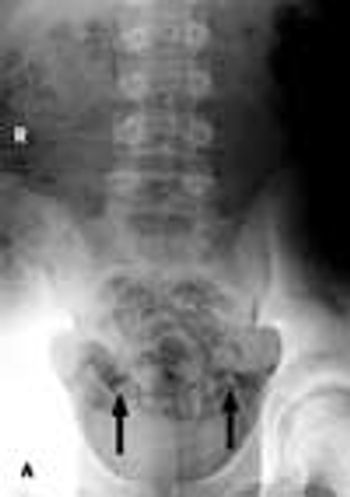

A 16-year-old boy complains of right lower leg pain that began after his first week at a summer basketball conditioning camp. Before he left for the camp, he was jogging off and on, averaging a few miles a week.

A 12-year-old otherwise healthy boy was referred to a sports medicine clinic for back pain of 7 months' duration. The pain, which originated to the right of his thoracic spine, was associated with shooting hockey pucks. Results of his physical examination were normal.